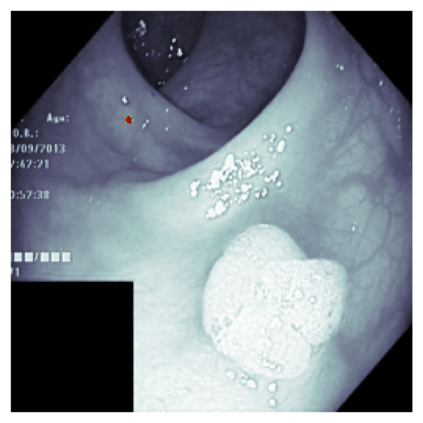

The sigmoid activation is the standard output activation function in binary classification and segmentation with neural networks. Still, there exist a variety of other potential output activation functions, which may lead to improved results in medical image segmentation. In this work, we consider how the asymptotic behavior of different output activation and loss functions affects the prediction probabilities and the corresponding segmentation errors. For cross entropy, we show that a faster rate of change of the activation function correlates with better predictions, while a slower rate of change can improve the calibration of probabilities. For dice loss, we found that the arctangent activation function is superior to the sigmoid function. Furthermore, we provide a test space for arbitrary output activation functions in the area of medical image segmentation. We tested seven activation functions in combination with three loss functions on four different medical image segmentation tasks to provide a classification of which function is best suited in this application scenario.